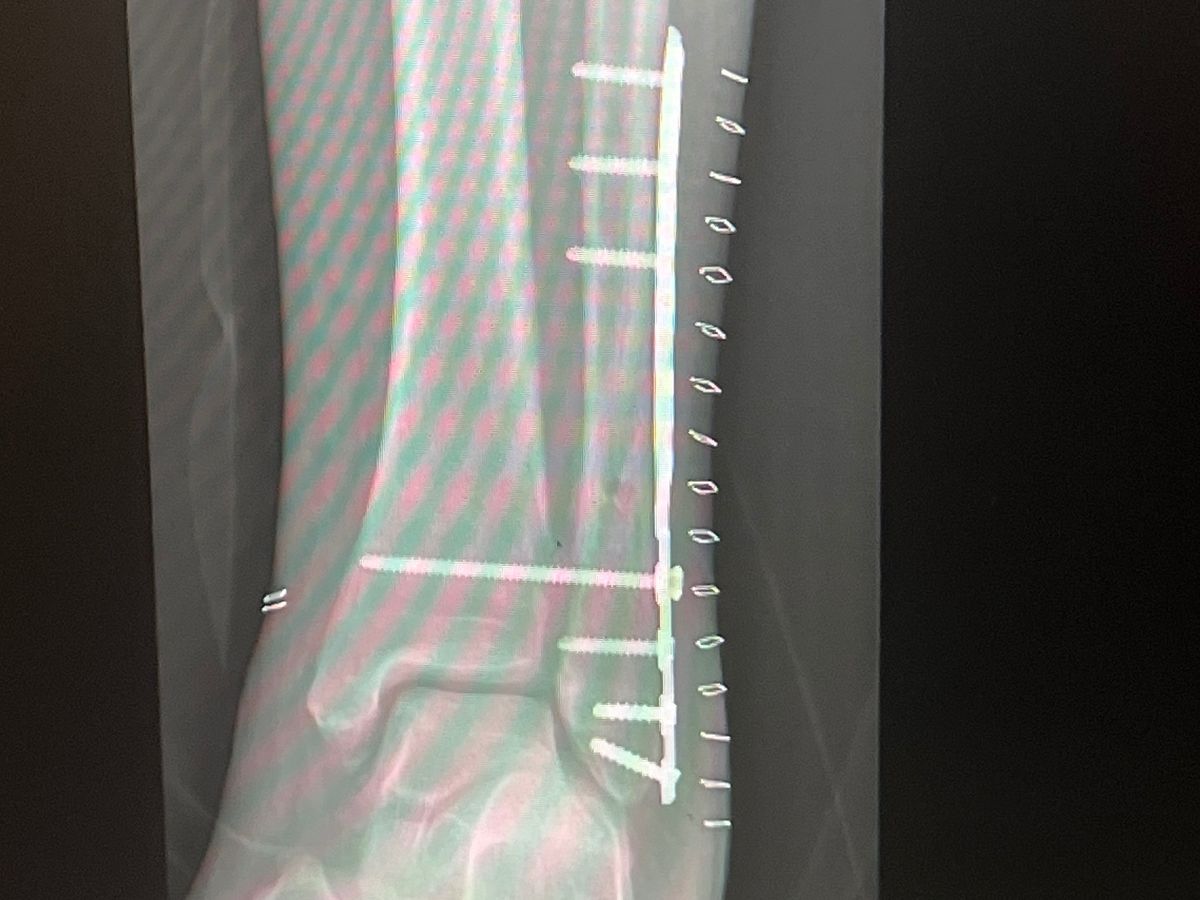

Hello, I’m Andre. I’m starting this for my mom; Gloria Michelle Freeman, she needs your help. She broke her leg back in November and had to have surgery. She wasn’t able to work till mid-January.

Now she has to have another procedure on her leg and doesn’t have the money. She doesn’t even have the money to get her regular monthly meds from the pharmacy. She doesn’t have money to pay her doctors appointments or physical therapy. She’s literally broke! Please find it in your hearts to help her out.